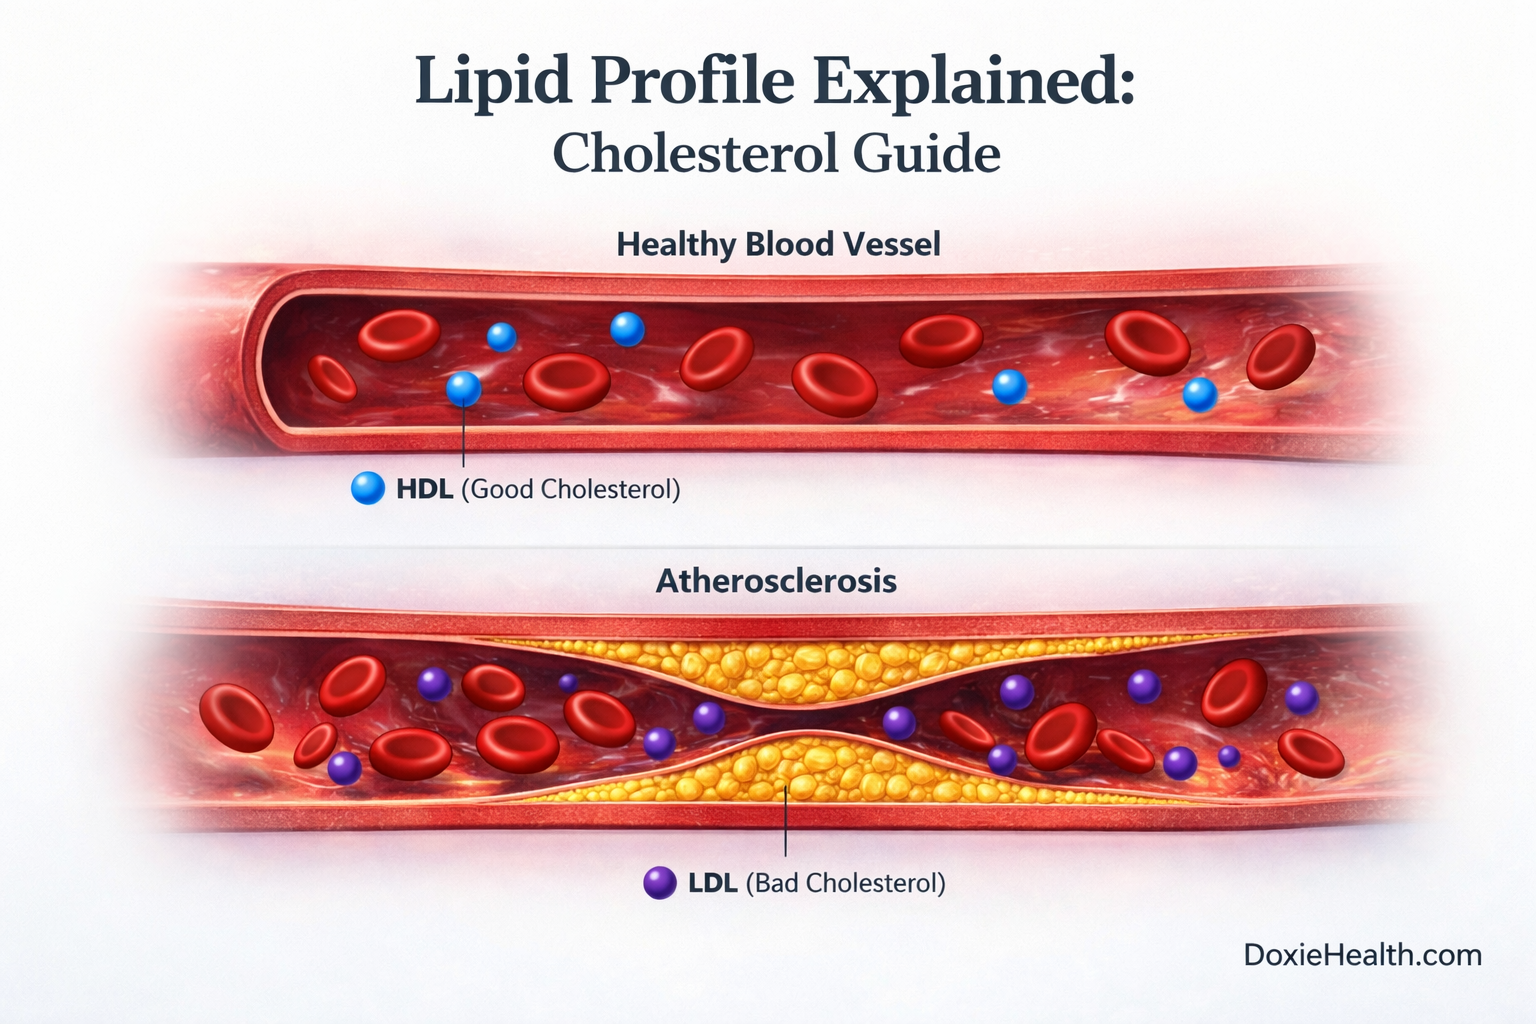

When LDL Becomes a Problem

In normal amounts, LDL is useful. But when LDL levels are high, excess cholesterol can start depositing in artery walls. Over time, this can lead to plaque formation, a process known as Atherosclerosis.

HDL — The Cleanup System

To balance this, the body uses HDL (High-Density Lipoprotein).

HDL collects excess cholesterol from the bloodstream and transports it back to the liver for removal. This protective process is known as reverse cholesterol transport.

Complications: Persistently high total cholesterol drives atherosclerosis- the gradual build-up of fatty plaques inside artery walls -which raises the risk of heart attack, stroke, and peripheral artery disease over time.

When LDL levels are too high, excess cholesterol is deposited into artery walls, forming plaques — a process called atherosclerosis. It is the single most important number on your lipid profile.

HDL (High-Density Lipoprotein) works in the opposite direction to LDL. It collects excess cholesterol from artery walls and transports it back to the liver for removal — a process called reverse cholesterol transport.

An HDL below 40 mg/dL is an independent risk factor for heart disease — even when LDL appears completely normal.

Low HDL below 40 mg/dL in men and below 50 mg/dL in women significantly raises cardiovascular risk.

Your lipid profile is a window into your long-term cardiovascular and metabolic health. Each marker tells a specific part of the story — and no single number gives the full picture.

LDL drives plaque build-up. HDL clears it. Triglycerides reflect your metabolic health. The ratios tell you how these markers relate to each other.